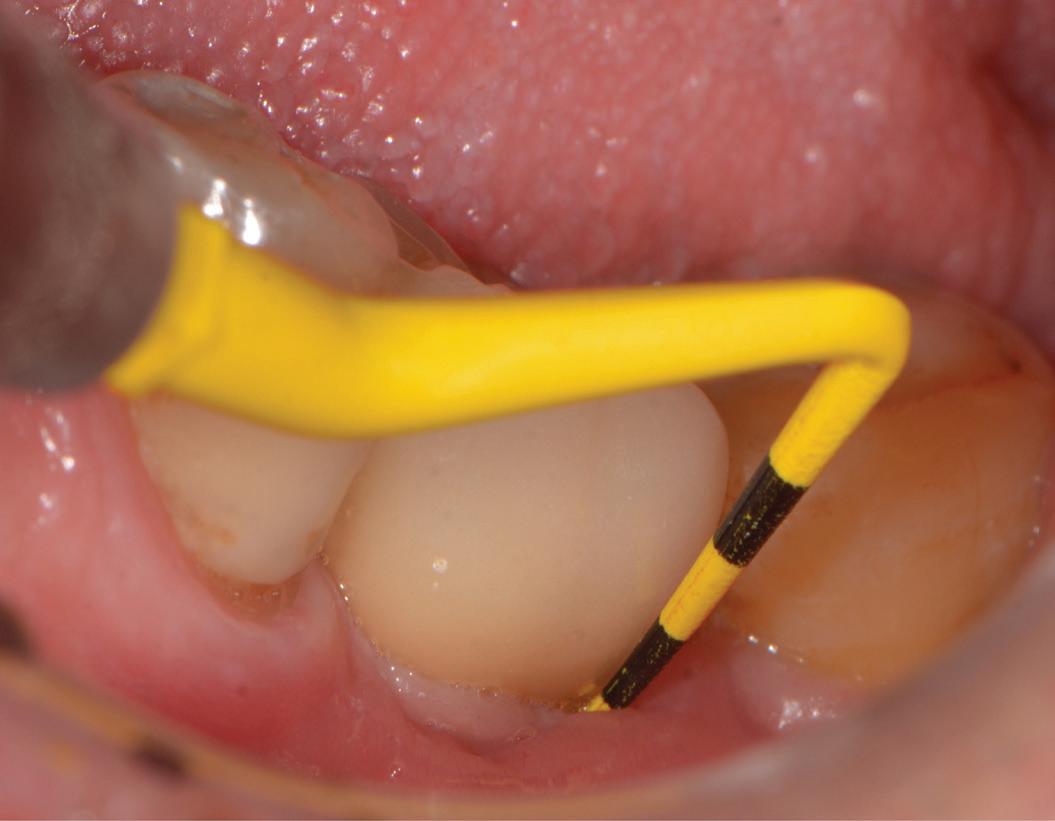

Clear aligner therapy and symptoms of temporomandibular disorders: a case report

Lina Sharab

Bushra Butul

Aqib Shafi

Jeffrey P. Okeson

SELF-INSTRUCTION EXERCISE GD538, 2 CE CREDITS, P. 53